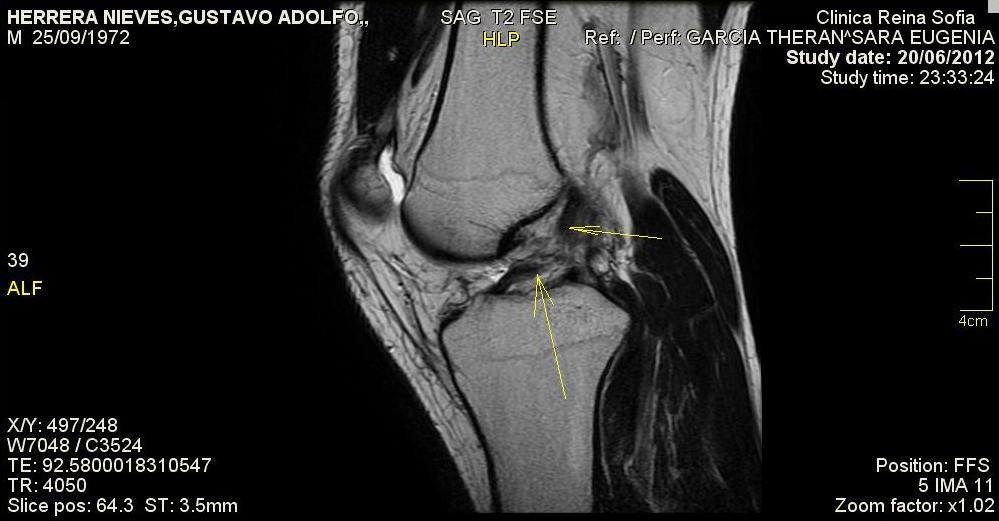

Ligamento Cruzado Anterior Roto Resonancia, Lesión del ligamento cruzado posterior ¿Cómo se ve en resonancia magnética, 14.1 MB, 10:16, 32,582, DOCTOR PAZ, 2020-06-24T00:02:48.000000Z, 3, Ligamento Cruzado Anterior: Antes de la Operación, lcant.blogspot.com, 999 x 521, jpeg, WebPor norma general general, una vez que la inflamación cede, las personas con un desgarro del ligamento cruzado anterior están pudiendo caminar. Pero es posible que sientan que la rodilla está inestable, no soporte el peso y provoque una pérdida del. WebEl diagnóstico de un ligamento cruzado anterior roto es clínico. (Fig 1) Resonancia magnética de la rodilla puede ser solicitada para confirmar el diagnóstico, para. WebSi se rompe un ligamento cruzado, la articulación de la rodilla se hincha considerablemente y se desarrolla un dolor punzante. En muchos casos, la rotura del ligamento cruzado se., 20, ligamento-cruzado-anterior-roto-resonancia, Novedades y Muebles WebPor norma general general, una vez que la inflamación cede, las personas con un desgarro del ligamento cruzado anterior están pudiendo caminar. Pero es posible que sientan que la rodilla está inestable, no soporte el peso y provoque una pérdida del. WebEl diagnóstico de un ligamento cruzado anterior roto es clínico. (Fig 1) Resonancia magnética de la rodilla puede ser solicitada para confirmar el diagnóstico, para. WebSi se rompe un ligamento cruzado, la articulación de la rodilla se hincha considerablemente y se desarrolla un dolor punzante. En muchos casos, la rotura del ligamento cruzado se.

WebLa resonancia magnética es la mejor imagen para comprobar el estado de los ligamentos, aunque existen casos en los que no se llega al diagnostico sino es con.

Webligamento cruzado anterior y menisco [quote="Fisio-Esceptico"]La cirugía te garantizará una rodilla más estable de por vida. Para una vida convencional y sin hacer. Web¿Cómo sabemos que el ligamento cruzado anterior está roto? En las primeras horas tras lesión traumática de LCA, se produce inflamación local y dolor . En. WebResonancia magnética. Corte sagital. Observa el bolígrafo: situado entre el ligamento cruzado anterior a tu izquierda y ligamento cruzado posterior a tu derecha..